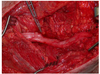

Which of the following conditions is a relative CONTRAINDICATION for use of the flap in the image shown for reconstruction of an 8 x 10-cm anterior ankle wound?

The correct response is Option D.

Diabetes mellitus can be associated with peripheral vascular disease, but by itself, would not prevent successful use of the reverse sural artery flap for foot or ankle reconstruction. Appropriate preoperative workup would include noninvasive ultrasound study of the lower extremity vasculature to prove the peroneal artery was patent.

The distally based sural artery flap receives its blood supply from a few sources, the most robust of which are perforators from the peroneal artery. The most distal of these perforators arise between 4 and 7 cm proximal to the lateral malleolus. Additional perfusion arises from neurocutaneous perforators from the sural nerve and venocutaneous perforators from the lesser saphenous vein.